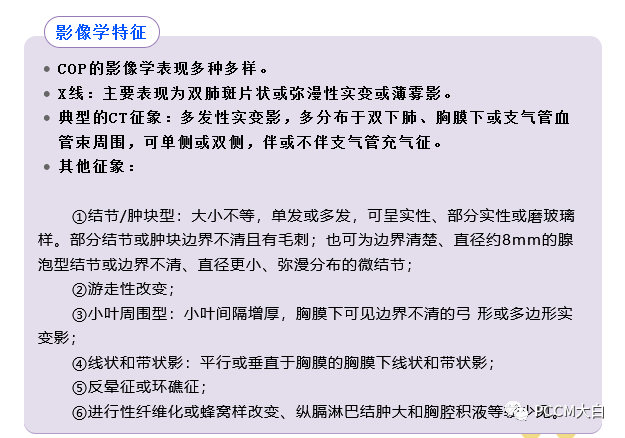

COP肺部CT表现多数为肺泡实变影,可从2cm至双侧广泛病变,病灶多位于胸膜下或肺野外带。病灶呈不规则斑片状,累及多个肺段。部分患者同时可见网状影、不规则线状影和结节影。网格状阴影较少见,很少有胸腔积液等胸膜渗出征象。

COP影像学特点为“五多一少”:

即多态性、多发性、多变性、多复发性、多双肺受累,蜂窝肺少见。具体如下:

①多态性:可呈斑片状、肺实变状、团块状、条索状、地图状、结节状、粟粒状、网织状、蜂窝状等各种形态,以前四种比例较高。每例患者多同时具有两种以上的形态。

②多发性:COP多为两肺多发性病灶。

③多变性:病灶有明显的游走性,具有此起彼伏的特点,多数病例在一周内可见观察到病灶的明显变化。抗感染治疗基本不影响病灶的变化。

④多复发性:文献报道的复发率多在13~58%之间。

⑤多双肺受累:两侧中下肺分布为主,占88%;沿着胸膜分布占96%,不累及胸膜占40%。

⑥蜂窝肺少见:仅有少数晚期重症COP出现蜂窝肺,发生率为4%。

通常情况下,提示COP诊断的第一线索来源于其影像学的特点,经过抗感染等治疗效果不佳,结合病理改变,排除其他疾患后诊断为COP。